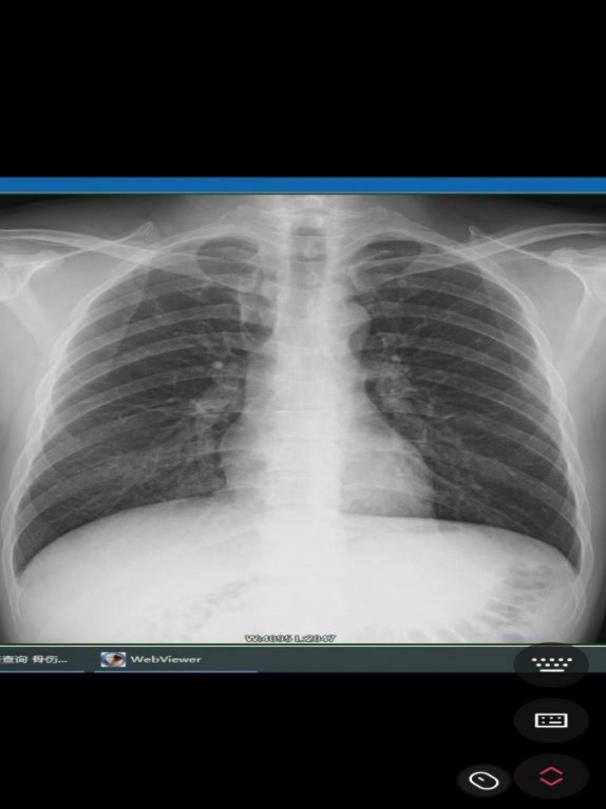

(术前DR片) ????????????????(术后DR片)

术后,匡先生病情稳定,复查DR颈部无异物,手术伤口处敷料包扎完好,干燥无明显渗出,伤口引流管通畅,经过医务人员的精心治疗和细心照顾,已于8月1日痊愈出院。